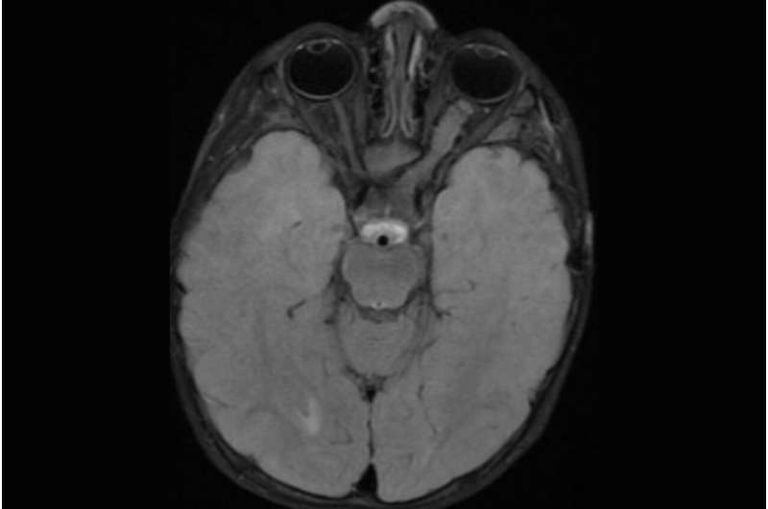

اكتشف باحثون في كلية الطب بجامعة واشنطن، أن دواء "لاموتريجين"، الذي يستخدم عادة لعلاج الصرع لدى الأطفال، يمكن أن يمنع تكوين ونمو أورام المخ لدى الأفراد المصابين بالورم الليفي العصبي من النوع الأول (NF1).

والورم الليفي العصبي من النوع الأول، هو اضطراب وراثي يؤدي إلى نمو الأورام على الأعصاب في جميع أنحاء الجسم، بما في ذلك الأعصاب البصرية.

وأظهرت الأبحاث السابقة التي أجراها الفريق أن "اللاموتريجين"، أوقف نمو الأورام الدبقية البصرية، وهي الأورام الأكثر خطورة المرتبطة بالورم الليفي العصبي من النوع الأول، وذلك عن طريق قمع فرط نشاط الخلايا العصبية.